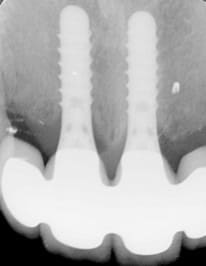

Oui, voici les radios

La CCM du 4 se voit facilement, les autres non, et pour cause, soit il y a du Margin (3), soit c'est de la prothèse supra implantaire et il y a donc plus de place en général pour que la prothésiste gère sa stratification et sa morpho

Oui et c'est bien de le rappeler !! hein c'est bien beau tout ça ... mais je suis sure que sur tout les cas présentés , il y a de tres belles préparations,polies, homothétique , de beaux congés sous gingivale. Alors oui en tant que céramiste c'est un régal de travailler sur de tels cas ... on peut multiplier les couches de céramique. Alors à ceux qui se diraient " mon prothésiste est nul" merci de prendre en compte ces données PRIMORDIALES à toute réalisations cosmétique : 1.5 mm d'épaisseur de céramique au collet , et on ne verra jamais de liseret grisâtre ..